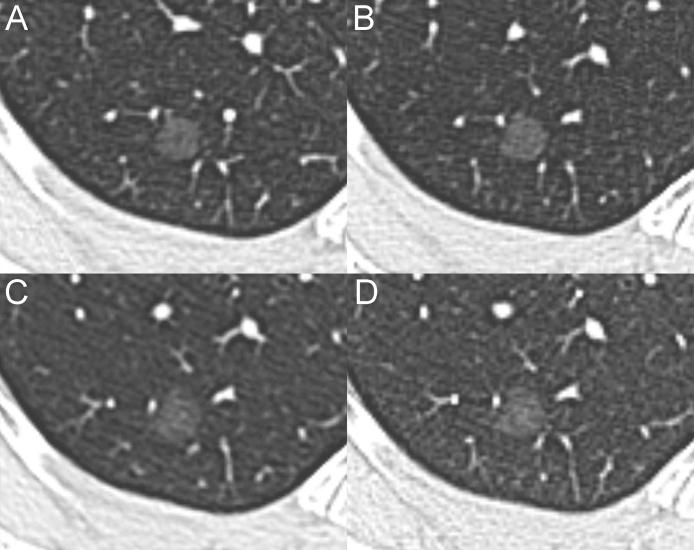

Persistent pure ground-glass nodules (pGGNs) typically show an indolent course with very slow growth rates. These slow-growing lesions exhibit different growth patterns regardless of their initial computed tomography (CT) features. Therefore, predicting the aggressive behavior of pGGNs on initial CT remains a diagnostic challenge. The literature reports that computerized analysis and various quantitative features have been tested to improve the risk stratification for pGGNs. The present article describes the long-term follow-up of two pGGNs with different behavior and introduces, for the first time, a new computerized method of analysis that could be helpful for predicting the future behavior of pGGNs.

持续性纯磨玻璃结节(pGGN)通常病程进展缓慢,生长速度极慢。这些生长缓慢的病变无论其初始计算机断层扫描(CT)特征如何,都表现出不同的生长模式。因此,在初始CT上预测pGGN的侵袭性行为仍然是一项诊断挑战。文献报道,已经对计算机分析和各种定量特征进行了测试,以改善pGGN的风险分层。本文描述了两个具有不同行为的pGGN的长期随访情况,并首次介绍了一种新的计算机分析方法,该方法可能有助于预测pGGN的未来行为。